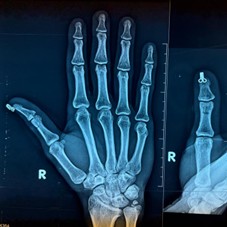

Fig.2: Day 5 post operative radiograph demonstrating maintained reduction and joint alignment

Five days post-application:

- The patient reported no pain or discomfort.

- The surgical site and nail bed showed no signs of ischemia, ulceration, or adhesive-related damage.

- Radiographs demonstrated maintained alignment of articular fragments and satisfactory reduction.

- No loosening or mechanical failure of the traction system was observed.